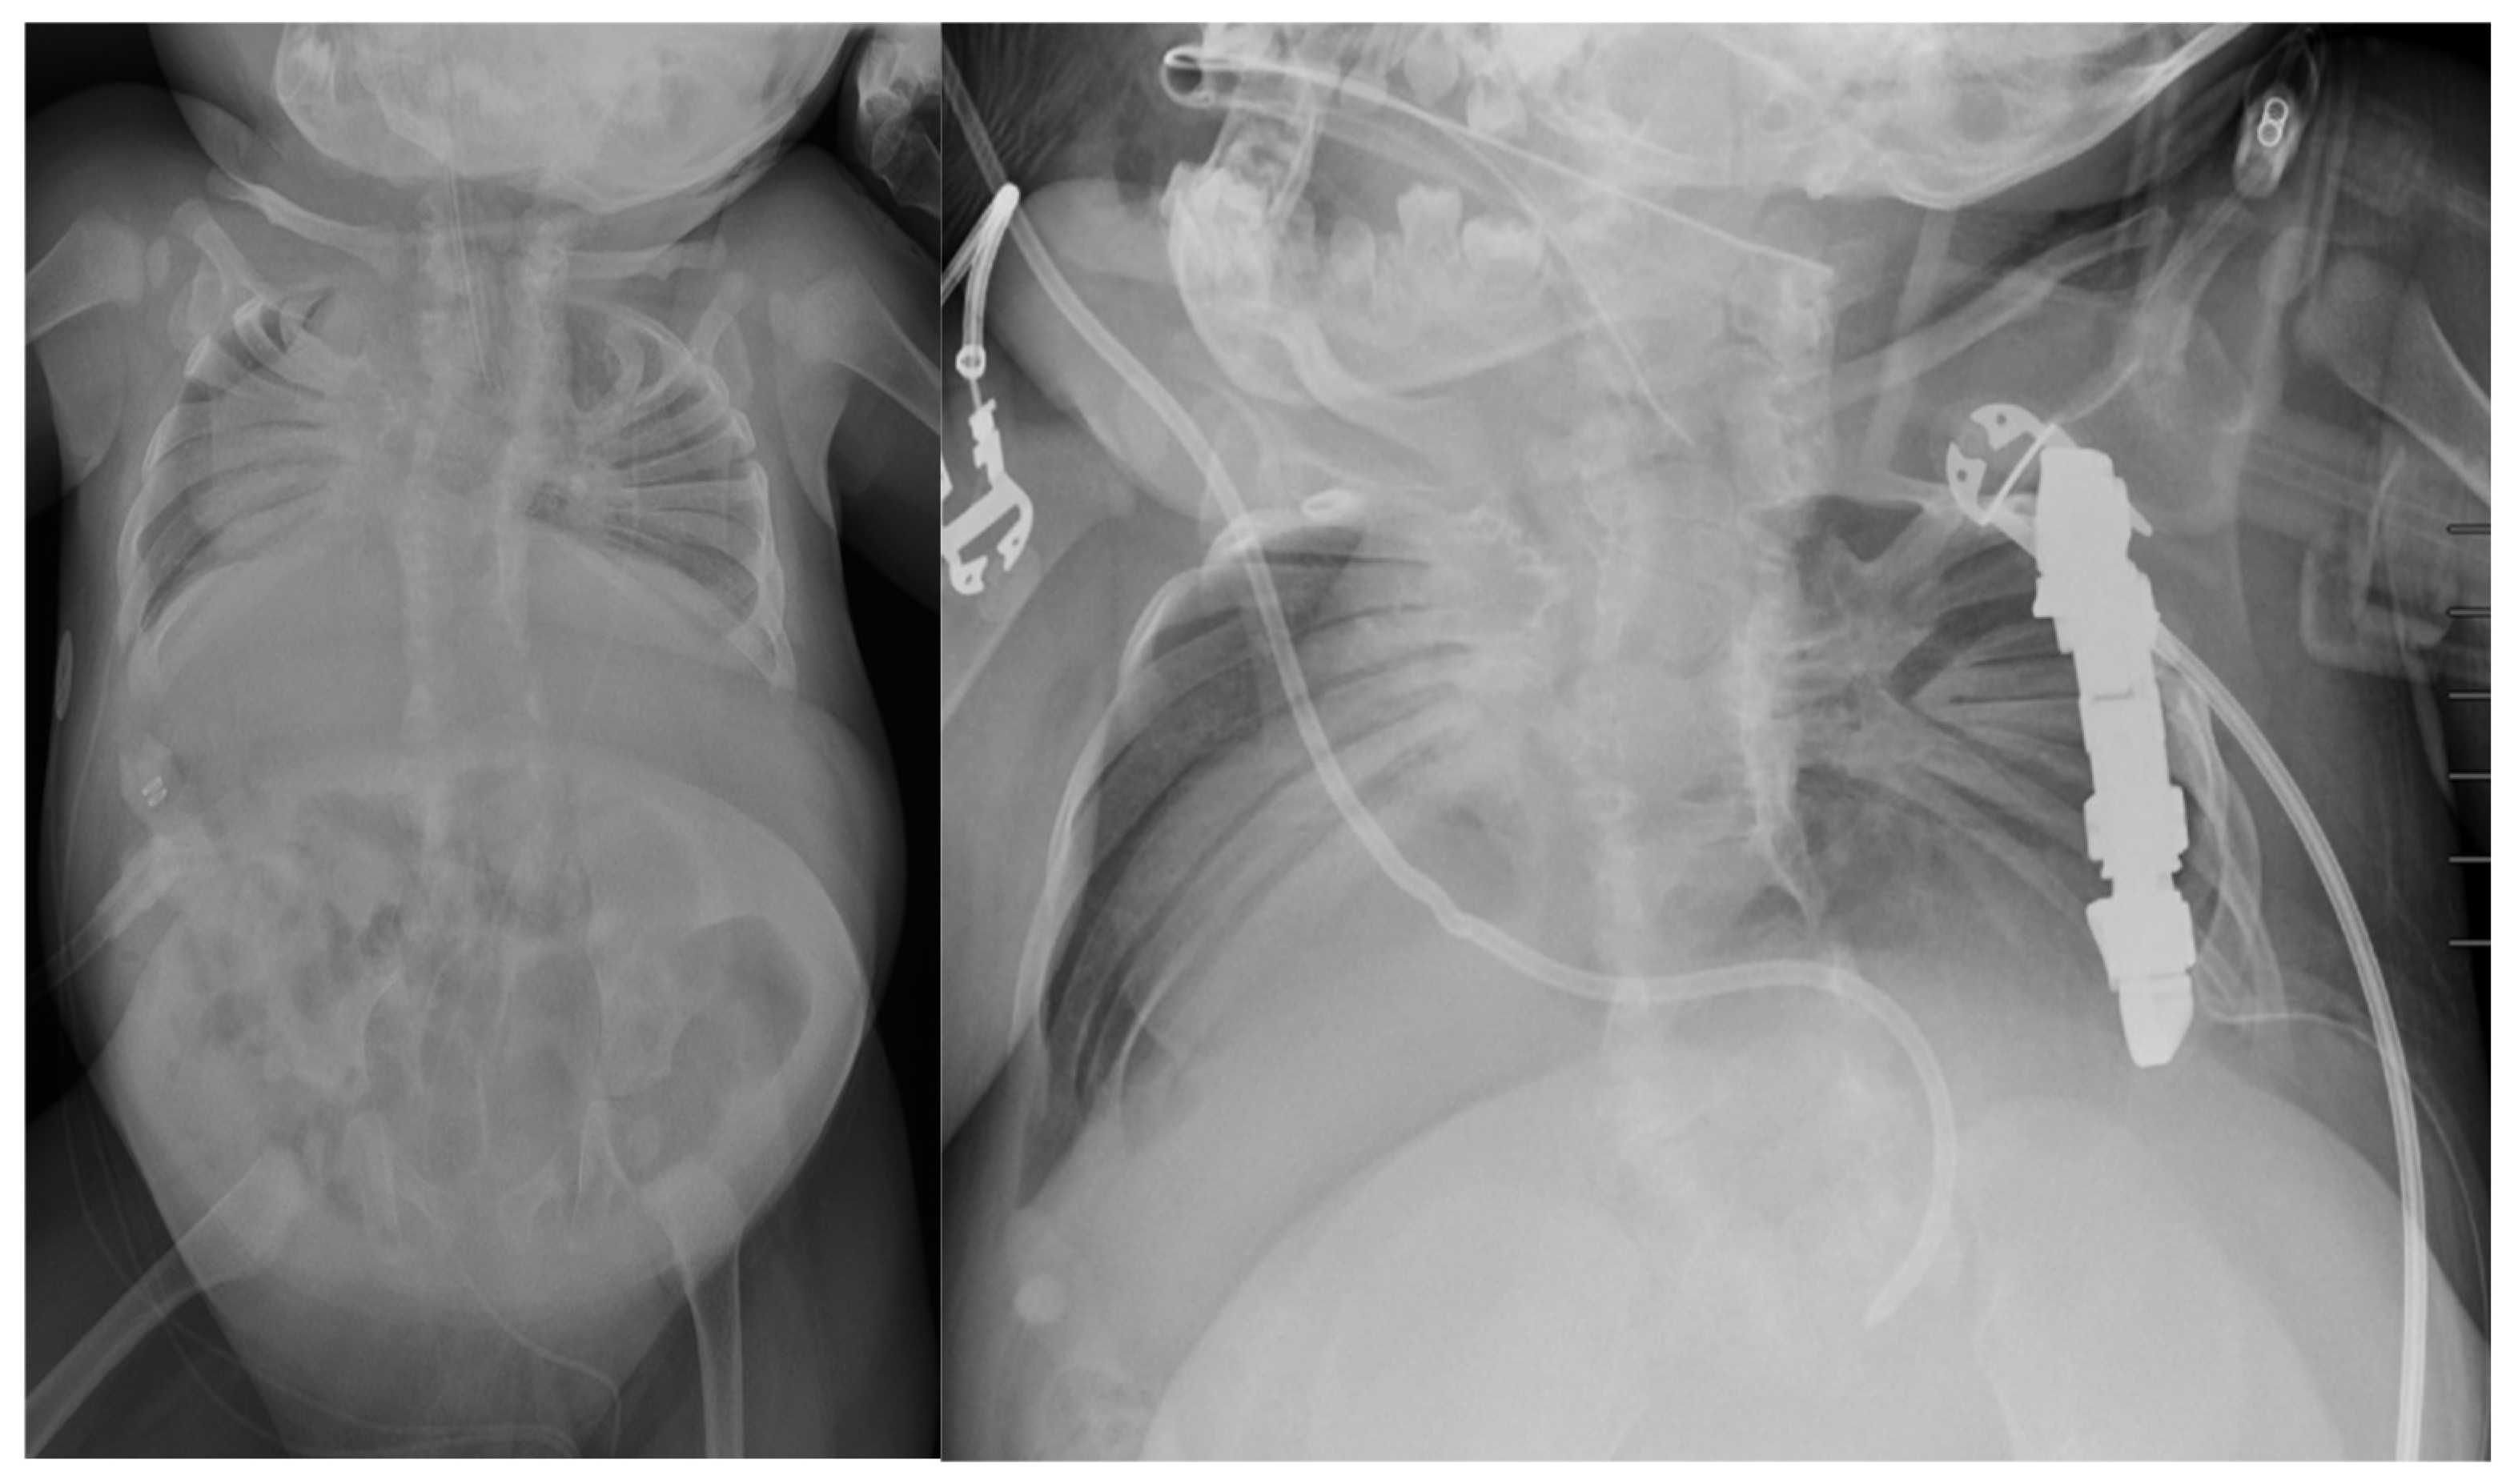

5. Surgical Management

- Lynn, A.M.; Budac, S. Jeune Syndrome (Asphyxiating Thoracic Dystrophy). In Essence of Anesthesia Practice; WB Saunders: Philadelphia, PA, USA, 2011; p. 222. [Google Scholar]

- Phillips, J.D.; van Aalst, J.A. Jeune’s syndrome: Congenital and acquired. Semin. Pediatr. Surg. 2008, 17, 167–172. [Google Scholar] [CrossRef]

- O’Brien, A.; Roth, M.K.; Athreya, H.; Reinker, K.; Koeck, W.; Patil, V. Management of TIS in Jeune Syndrome. J. Pediatr. Orthop. 2015, 35, 783–797. [Google Scholar] [CrossRef]

- Hennekam, R.C.; Beemer, F.A.; Gerards, L.J.; Cats, B.P. Thoracic pelvic phalangeal dystrophy (Jeune syndrome). Tijdschr. Kindergeneeskd. 1983, 51, 95–100. [Google Scholar] [PubMed]